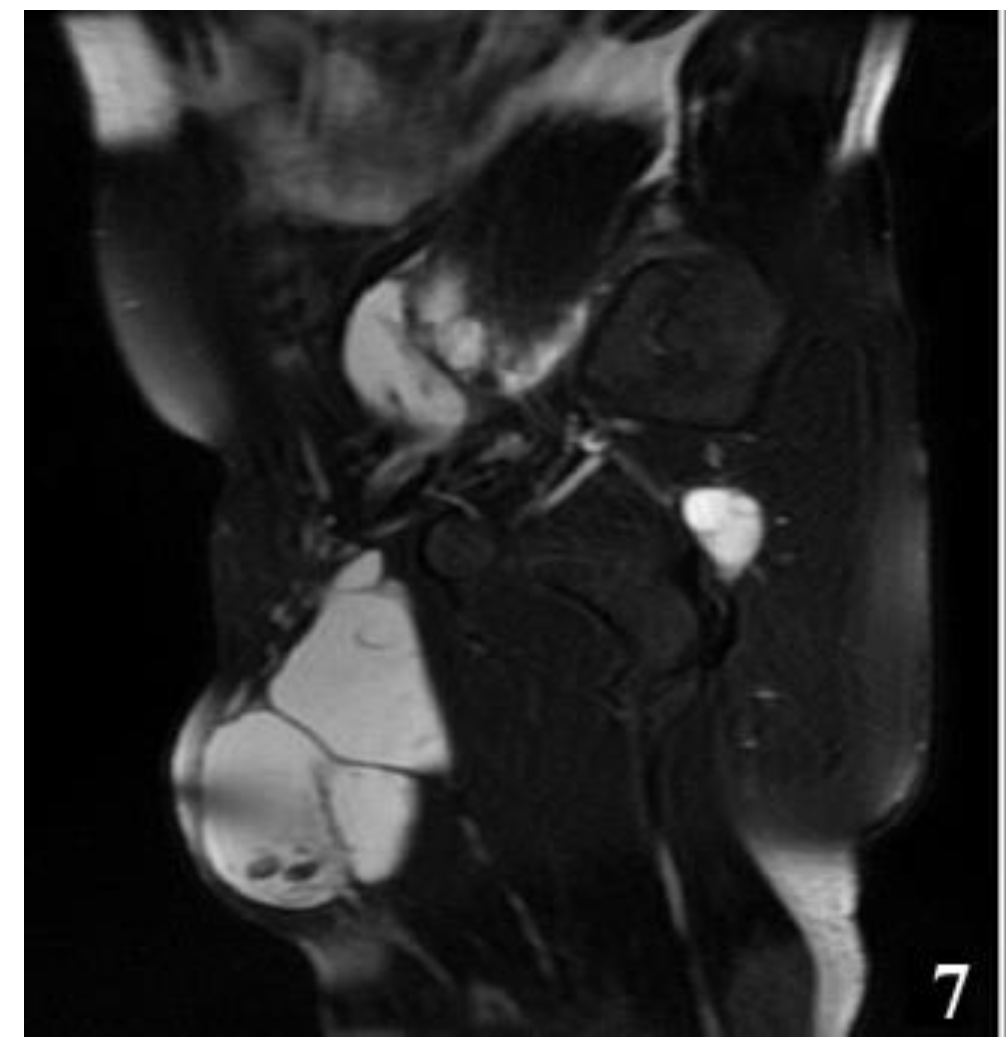

Figure 7.

T2W MRI sequence, sagittal—Hydatid cyst left iliopsoas muscle and left thigh (part 1).

The MRI examination was performed on two patients for surgical purposes, to establish the relationship with other organs or vital structures and to guide the indication and the surgical plan. It is important to note the case of a 32-year-old male patient, hospitalized for the presence of a tumor formation at the base of the left thigh, in which the native and contrast enhanced MRI examination of the pelvis and thigh revealed: urinary bladder without parietal thickenings or endoluminal pathological processes; seminal vesicles without pathological signal changes; prostate measuring 4.7/3.2 cm, homogeneous, without pathological contrast plugs; without suspicious adenomegaly at the pelvic level; replacement process of polylobate space, which is relatively well demarcated, predominantly with fluid signal, multiple septate, without diffusion restriction, with gadophilia present at the peripheral and intralesional septal level, starting from the vicinity of the psoas and iliac muscle on the left side and extending into caudal direction through the anterior portion of the inguinofemoral region on the left side to the proximal region of the left thigh, and coming into contact with the common iliac, external iliac and femoral vessels on the left side (apparently with preserved flow at their level and with the apparently left femoral diaphysis but no macroscopic invasion phenomena at this level); previously described space-replacing process, which extends over a cranio-caudal distance of approximately 33 cm and shows inhomogeneous signal at the level of some of the intralesional cystic areas; deep to the gluteus maximus muscle on the left side, a relatively well-defined area can be seen, with a polylobate contour, multiple septa, with a similar appearance to the previously described space-replacing process, with dimensions of 2.9/2.75 cm—possibly parasitic cystic lesions (Figure 4, Figure 5, Figure 6, Figure 7, Figure 8 and Figure 9).